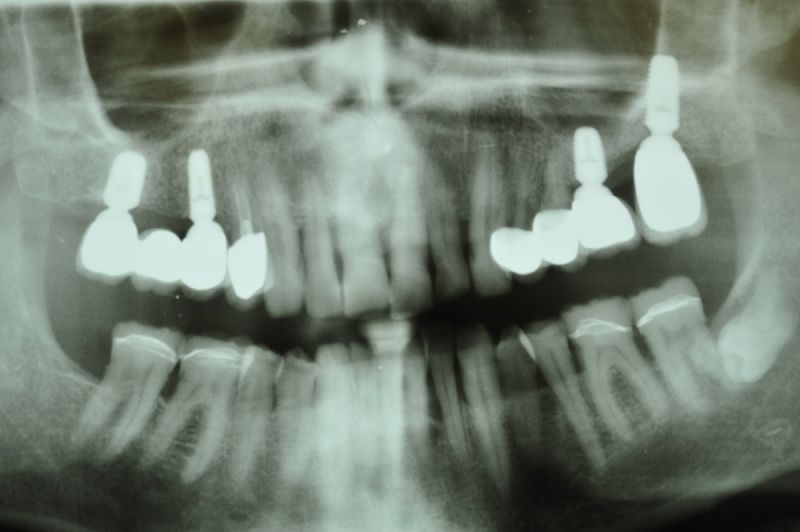

73 jähriger CMD-Patient im Recall

Der Patient hat vor 5 Jahren eine äußerst umfangreiche und komplexe CMD-Behandlung abgesclossen und befindet sich seitdem in einem engmaschigen vierteljährlichen Recall!

Seit 5 Jahren ist der Zustand des Patienten vollkommen unverändert!

Die aktuellen Taschentiefen liegen bei 2 Millimeter! Auch im Bereich der Implantate!

Das Allerwichtigste bleibt aber der engmaschige, vierteljähliche Recall, der aus mehr besteht, als nur einem Zahnsteinentfernen! Wichtig ist die fortlaufende Dokumentation der verschiedenen Parameter der parodontalen Gesundheit und genauso wichtig eine Röntgenkontrolle etwas alle ein bis eineinhalb Jahre.